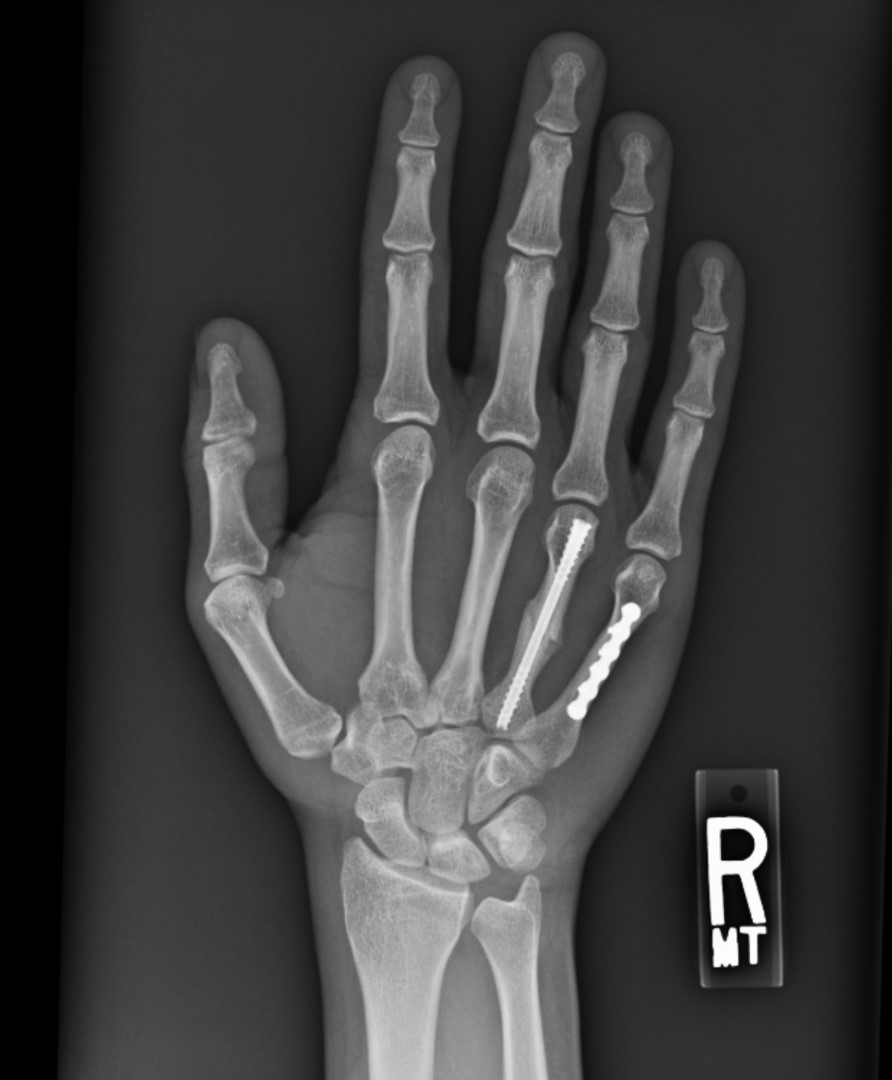

From fieldorthopaedics.com

NX Nail for fixation of displaced 4th metacarpal shaft fracture. Exsomed Metacarpal Nail innate is an intramedullary threaded nail designed specifically for metacarpal fractures to provide surgeons with a. innate is a stainless steel nail designed for fixation of metacarpal and metatarsal fractures, nonunions, arthrodesis, and. the exsomed innatetm threaded intramedullary nail (exsomed, aliso viejo, ca, usa) was developed with tall threads, a diameter fitting the metacarpal. innate is. Exsomed Metacarpal Nail.